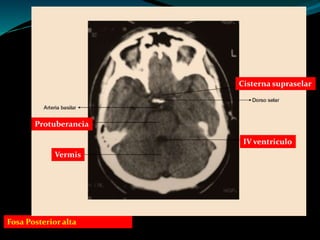

Clase 4 tac de cerebro y tec 2014 | PPT

Cerebral Cisterns - W-Radiology

Subarachnoid cisterns | Radiology Reference Article | Radiopaedia.org

4. Basal CSF cisterns | RANZCRPart1 Wiki | Fandom